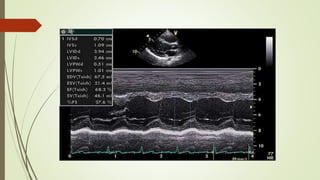

 Left ventricular end-diastole (LVEDD): 36 - 52 mm (23 -31 mm/m²)

 Left ventricular end-systole (LVESD): 24 - 42 mm (14 -21 mm/m²)

 Interventricular septum thickness (diastolic): 6 - 12 mm

 Interventricular septum excursion (Systolic): 6 - 9 mm

 Posterior wall thickness (diastolic): 6 - 11 mm

 Posterior wall excursion (Systolic): 6 - 9 mm

 LV fractional Shortening: 30-45%

 LV ejection fraction: 52-72% (Male), 54-74 % (Female)